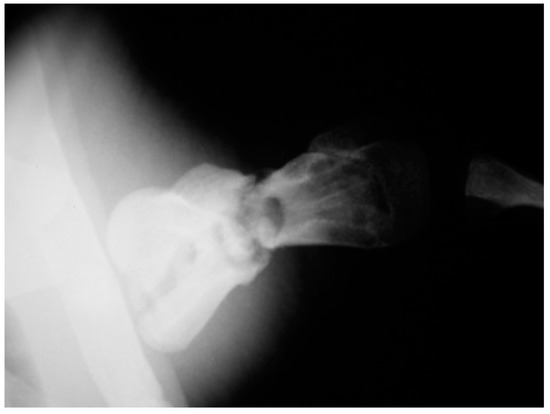

The post-operative radiographic examination confirmed the correct reduction of the diaphyseal fracture, bone realignment, and the good fixation of the detached distal epiphyseal stump (Figure 3). Fifty days later, the X-ray follow-up showed persistent stability of the joint and bone sclerosis, near the diaphyseal fracture site. After 70 days, the turtle could swim and move around comfortably; radiographic examination showed a better filling of the diaphyseal fracture line and almost complete repair of the epiphysis (Figure 4). Four months after surgery, the animal was in good general condition and had recovered the right front flipper’s normal function. Radiography showed a complete repair of the epiphyseal fracture and remodeling of the normal bone architecture, while the diaphyseal fracture still lacked unifying bone callus tissue (Figure 5). After one year, the flipper showed complete clinical recovery without signs of pain, and radiologically the fracture site was fixed, showing signs of remodeling of the fracture stumps, areas of thickened fibrous tissue, but still no appreciable unifying bone callus (Figure 6a). The good positioning and tightness of the means of fixation were radiologically confirmed, but the surrounding bone reabsorption and decalcification processes were evident. Removal of the intramedullary pins was deemed necessary. Radiograms performed after removal of the pins showed the presence of calcified sites within the tissue interposed between the two bone stumps (Figure 6b). Two years after the procedure, radiographic follow-up demonstrated a better filling of the fracture line and further remodeling of the stump margins (Figure 7).

Figure 7. Twenty-four-month follow-up (caudocranial view) demonstrating a better filling of the fracture line and further remodeling of the stump margins.